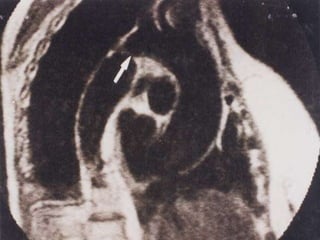

Historia Natural: Se desarrolla gradualmente La p resenta ció n  suele ocurrir entre  los  15  y  30  años La lesión más asociada es la   aorta bivalva   desde un 50% hasta un 80%. Más común en el sexo masculino En mujeres puede sugerir   Síndrome de  Turner .

Aorta bivalva

Ecocardiogram a : Puede evitar el cateterismo en casos característicos Es de importancia para diagnosticar  Aorta bivalva.

ECO: Aorta bivalva

Historia Natural: Sedesarrolla gradualmente La p resenta ció n suele ocurrir entre los 15 y 30 años La lesión más asociada es la aorta bivalva desde un 50% hasta un 80%. Más común en el sexo masculino En mujeres puede sugerir Síndrome de Turner .

Ecocardiogram a :Puede evitar el cateterismo en casos característicos Es de importancia para diagnosticar Aorta bivalva.